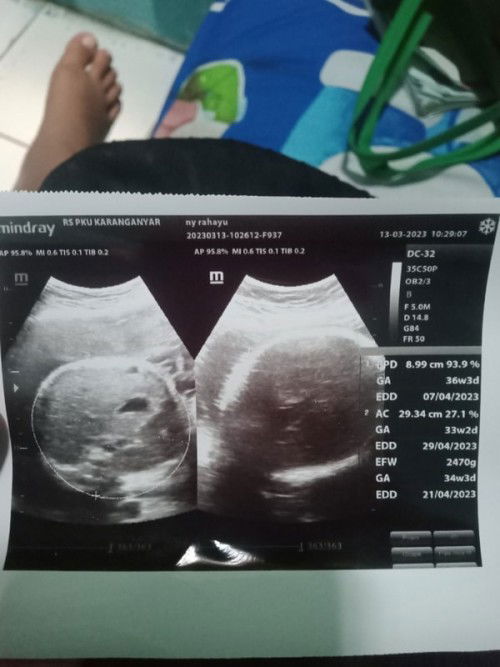

Hasil usg kehamilan

Bun mau tanya ini bacanya gimana ya berat,hplnya sama usia kehamilan?itu yg diusg kepala sama apanya ya Bun kok ada bolongnya